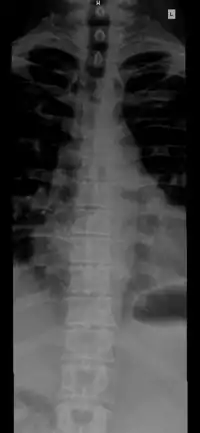

Vertebral column.